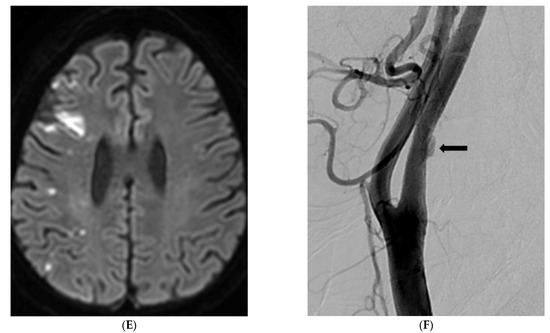

- Park, J.S.; Kwak, H.S.; Lee, J.M.; Koh, E.J.; Chung, G.H.; Hwang, S.B. Association of carotid intraplaque hemorrhage and territorial acute infarction in patients with acute neurological symptoms using carotid magnetization-prepared rapid acquisition with gradient-echo. J. Korean Neurosurg. Soc. 2015, 57, 94–99. [Google Scholar] [CrossRef]